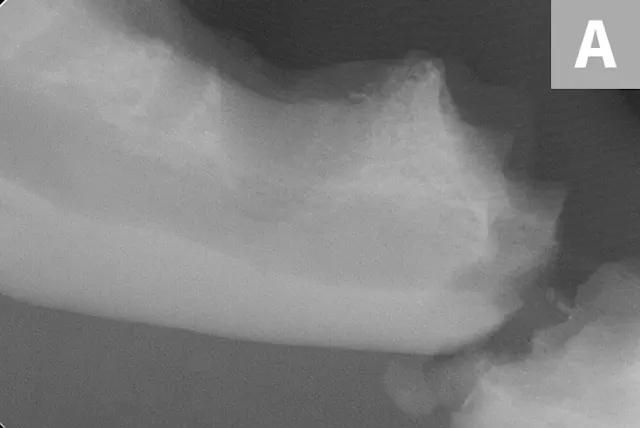

A complete oral examination confirmed stage 4 periodontal disease of numerous teeth (ie, first through fourth maxillary premolars, all maxillary molars, both maxillary canines, all remaining incisors). Dental radiographs confirmed bilateral mandibular fractures at the mesial root of the right mandibular first molar and distal root of the left mandibular first molar (Figures 1 and 2).

Preoperative intraoral dental radiographs of the right (A and B) and left (C) mandibular first molars. There is marked alveolar bone loss secondary to periodontal disease (blue lines), as well as pathologic, iatrogenic mandibular fractures (arrows).